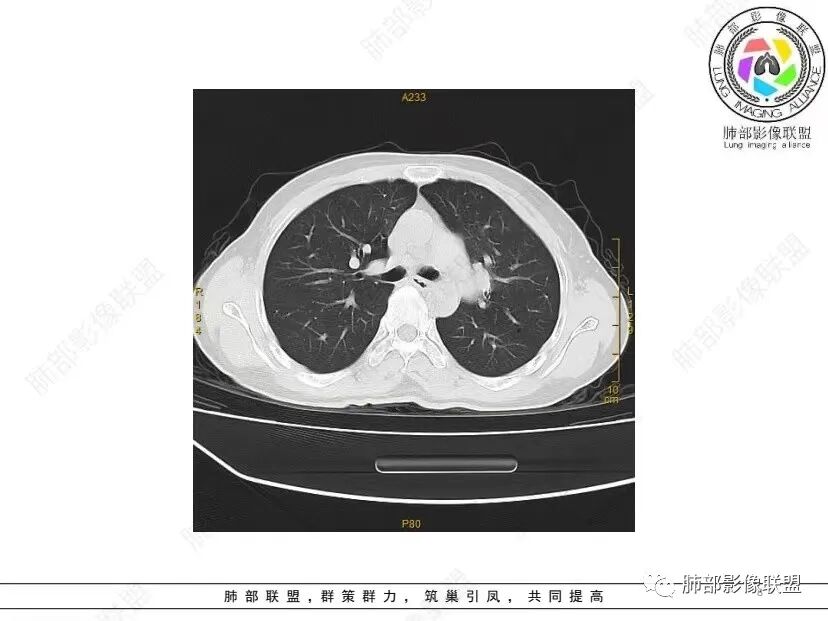

秦化君: 晨读 双肺不均匀散在多发囊状影,大小不等,部分囊形态欠规整,壁薄均匀,部分囊胸膜下平行。双肺少许斑片状磨玻璃影,边缘模糊。考虑BHD综合征。鉴别PCP,LIP。

红日初升: 中年女性,双肺多发气囊,背景干净,大小不一,下肺韧带旁较大,考虑BHD,鉴别LIP、LAM

玫: 晨读:女,49岁,双肺散在多发囊性病灶影,薄壁,部分层面病灶形态欠规整,右肺下叶少许磨玻璃影,边缘模糊,考虑LIP,鉴别BHD。

宇宙: 中年女性,两肺多发大小不等薄壁囊状影,两肺纵膈胸膜下分布明显,考虑BHD,鉴别LAM

放射线 (王秀仙): 双肺多发囊状影,大小不等,部分囊壁呈磨玻璃样,另双肺见斑片状磨玻璃影,边缘模糊。女性,考虑LIP,鉴别BHD

段建民: 双肺多发囊状影,多成圆形或三角形,囊壁薄且均匀,正常肺野内透过度尚可。双肺多发囊状影的鉴别,中心肺气肿,间隔旁肺气肿,PJP,支气管扩张,囊肿,支气管肺发育异常;LAM LIP PLCH BHD;囊腔腺癌,转移瘤,血播金葡菌……

本病例首先考虑BHD。

良孑: 两肺多发含气囊腔,大小不等,囊周见血管伴行,首选BHD,建议查双肾情况,鉴别Lam

这个病例目前影像特点,多囊,囊主要位于下肺,胸膜下及小叶核心为主

伴随少许索条,而且这些病灶与囊不一定有相关性

囊的分布,PLCH基本可以排除

囊壁薄且均匀,光滑,形态规则,基本除外恶性

单纯囊,无斑片及其他实性病灶,感染不支持,可能的是:LAM、BHD、LIP

从囊的分布、大小,BHD可能性可能大一些,但是LIP、LAM都可以这样表现,具体诊断应该是这三种之一,影像缩小到这里我觉得就差不多了,结合临床考虑就行,不支持靠影像强下结论。